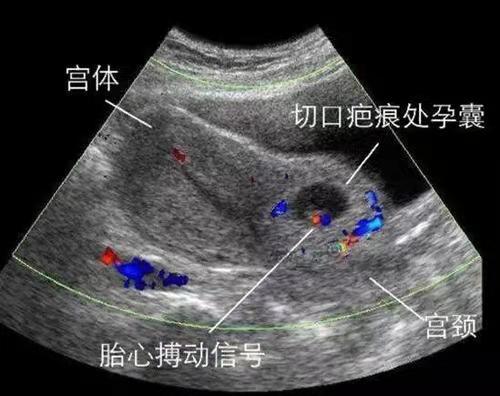

- 不幸被"III型疤痕妊娠"盯上瑞博婦產(chǎn)科成功取 閱讀:184人

- 隨著國家二胎政策的逐步放開, 很多年輕的夫婦想要二寶的心蠢蠢欲動, 疤痕妊娠也因此浮現(xiàn)在我們眼前。 說到疤痕妊娠, 很多人也許很陌生, 因?yàn)樗霈F(xiàn)的概率很低很低。 疤痕妊...【閱讀全文】